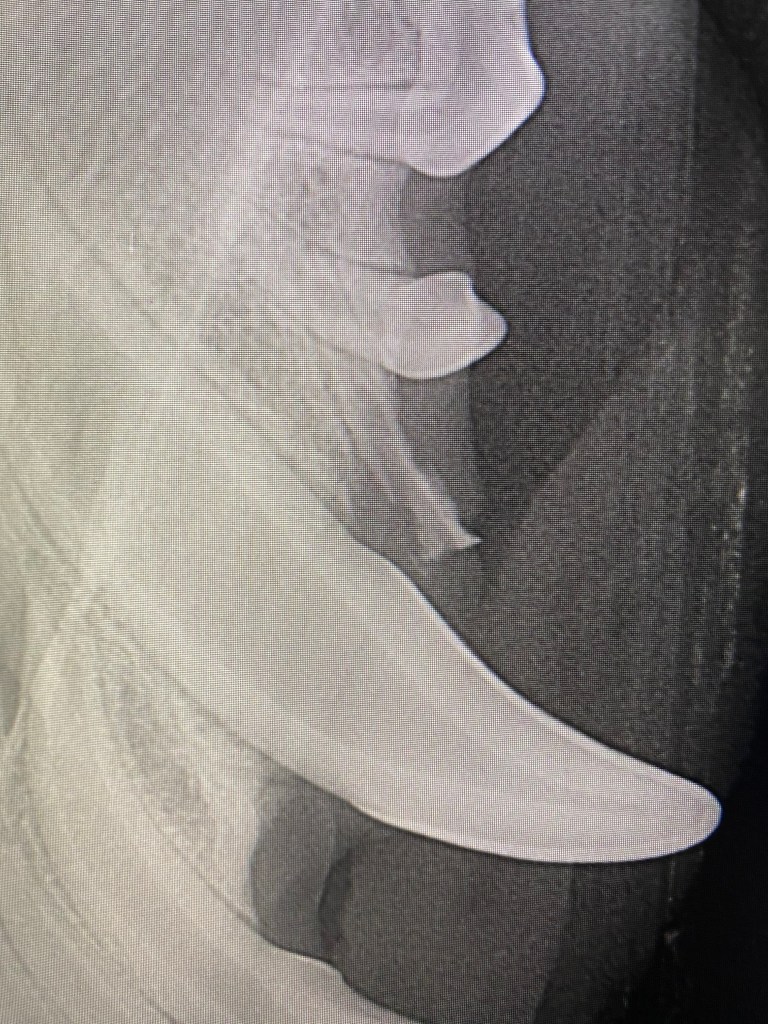

There was an anorexic 40 year old tortoise that had to be stomach tubed following her hibernation,

a bullterrier with a toxin induced life threatening hyperthermia, following the ill advised raiding of a litter bin

and a bitch spay that required an additional root extraction, which I would have overlooked without the brilliant nurse that was on duty that day ……